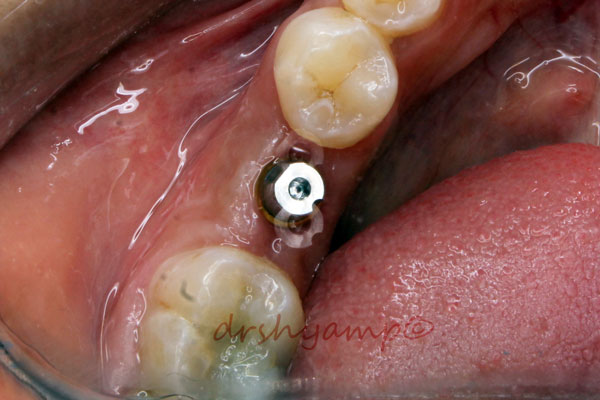

Screw Retained Dental Implant Crowns

-

Screw Retained Dental Implant Crowns